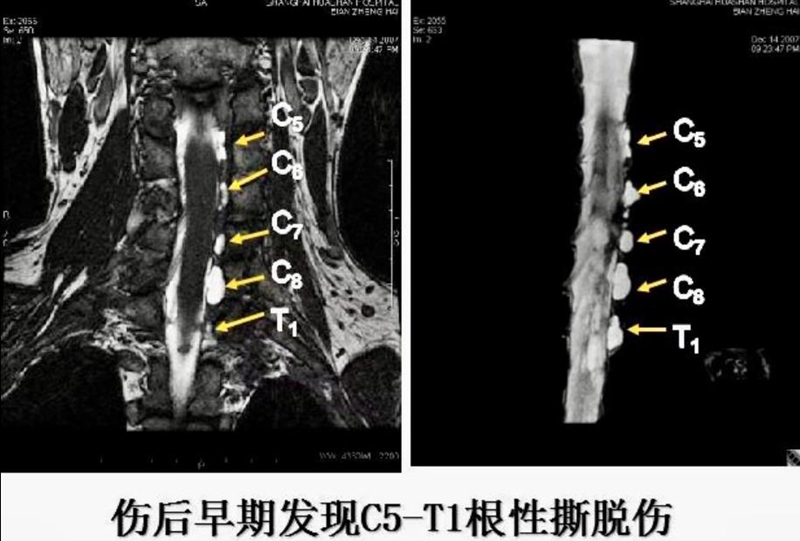

临床意义:早期诊断

MRI:同时显示节前节后影像,无创伤,准确可靠。

4、臂丛神经根性撕脱伤

颈神经根在脊髓部位的丝状结构断裂,术中在椎孔附近可见撕脱的脊神经节,有时各神经根外观正常,在椎孔内断裂。

7,全臂丛(C5-T1)根性撕脱伤

病史特征:上肢遭受对撞或牵拉暴力较大,持续时间较长,常伴有昏迷及多发性骨折;

上肢除臂内侧感觉存在外,余均消失;

临床检查:有上下干根性撕脱的典型体征,耸肩功能严重受限,Horner氏征阳性。